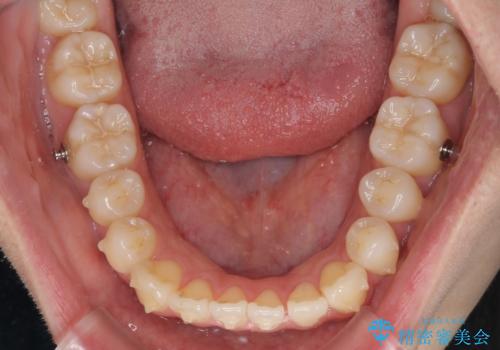

オープンバイトでかみにくい インビザラインによる矯正治療

- 矯正装置

- インビザライン

- 治療期間

- 11ヶ月

- 前歯の上下スペースによる食べにくさを気にして来院された患者様です。

インビザラインにより上下の前歯の隙間を閉じていくこととしました。

上下の奥歯を圧下させるようにすることで、前歯を接触させるように計画しました。

上下の隙間に舌が入り込むことがオープンバイトの原因であったため、舌の筋肉のトレーニングも並行して行い、後戻りの抑制を図りました。